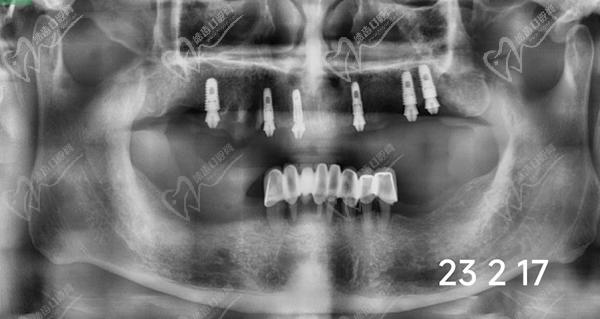

1、術(shù)前檢查和評估:進(jìn)行X光片、CT等影像學(xué)檢查,以確定患者的牙槽骨質(zhì)量和數(shù)量,為手術(shù)方案的指定提供數(shù)據(jù)支持。一般家里的老人患有基礎(chǔ)疾病的只要身體健康、口腔條件達(dá)標(biāo)都可以做,對全口牙齒重度松動的中青年患者亟需修復(fù)的可以做。

重度牙周炎會導(dǎo)致牙齒松動、脫落和牙槽骨的破壞。全口即拔即種種植牙適用于牙周炎患者,可以在一次手術(shù)中同時(shí)拔除松動的牙齒并植入種植體。在手術(shù)前,需要進(jìn)行詳細(xì)的口腔檢查和評估,包括X光片、CT等影像學(xué)檢查,以確定患者的牙槽骨質(zhì)量和數(shù)量。在手術(shù)中,局部麻醉后拔除松動的牙齒,然后在拔牙后的創(chuàng)口內(nèi)植入種植體,并進(jìn)行縫合。術(shù)后需要指導(dǎo)患者進(jìn)行日常護(hù)理和藥物治療,確保創(chuàng)口愈合良好。

牙友1、前天結(jié)束的全口種植牙,拔牙加同期種12顆瑞士士卓曼,即刻負(fù)重!全口牙周炎伴隨多顆牙松動且骨量不足等問題,普通的種植手術(shù)無法滿足生活需求,想要做即拔即種即刻戴上臨時(shí)牙,因?yàn)槌R?guī)的植骨手術(shù)需要等待很長時(shí)間。經(jīng)過正規(guī)醫(yī)院骨質(zhì)評估分析,上頜AO4+兩邊穿翼手術(shù),患者手術(shù)結(jié)束當(dāng)天就可以正常用牙,本人表示非常高興和滿意!感謝醫(yī)院團(tuán)隊(duì)協(xié)作!